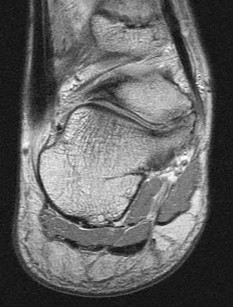

Figures 1a through 1c

Calcaneonavicular (CN) coalition

- Calcaneonavicular (CN) coalition**_

Tarsal coalitions occur when primitive mesenchymal cells fail to differentiate and form the

normal articular separations between the tarsal bones of the hindfoot. Overall incidence is difficult to determine because many affected people are minimally symptomatic or asymptomatic. Symptomatic tarsal coalitions typically present in adolescents as a painful flatfoot; however, there are a number of possible presentations, and occasionally symptoms do not appear until adulthood. Most tarsal coalitions are between the calcaneus and the navicular (CN) and the talus and the calcaneus (TC). Although most TC coalitions are across the middle facet, posterior facet coalitions do occur. Plain radiographic evaluation of suspected tarsal coalition is the mainstay for diagnosis. However, coalitions can be bony or fibrous, and making the diagnosis can be difficult. The addition of CT images to distinguish bony definition and MR images to decipher soft tissue can aid in diagnostics. Bony coalitions appear as definite bony bridging between the bones, while fibrous coalitions are suspected when distortion of the bony anatomy is seen. Bony coalitions are best seen on the oblique view (CN) and Harris axial view (TC). There are a number of secondary signs such as the anteater (AE) sign (elongation of the anterior process of the calcaneus as it extends to the navicular as seen on the lateral view [CN]). talar beaking (traction spur of the talar neck thought to result from abnormal stresses as seen on the lateral view [both CN and TN]), and the “C” sign (a continuous cortical contour from the medial talus to the sustentaculum tali [ST]) as seen on the lateral view (TC). A number of newer signs are not as well known, such as a broad mediolateral dimension of the navicular on the anteroposterior (AP) view (the

navicular is wider than the talar head [CN]), nonvisualization of the middle facet on the lateral view (TC), the brick sign (a normal ST is flat, but a distorted ST is enlarged and curved [CN]), and a tapered lateral navicular bone as seen on the AP view (the medial navicular [CN] is much thicker than the lateral navicular).

Figure 1a shows talar beaking (TB), an AE, and an open middle facet (MF). Figure 1b shows a wide navicular (WN), and Figure 1c shows an abnormal articulation between the calcaneus and the navicular, all consistent with a CN coalition.